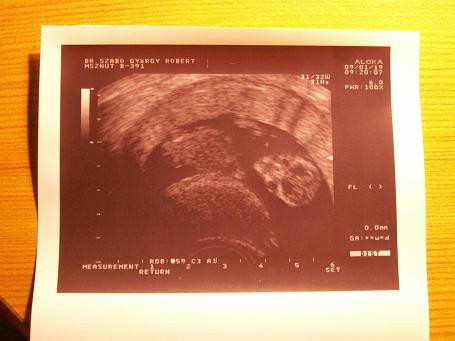

Kincsem 7.5cm a 13. héten

Kincsem 7.5cm a 13. héten